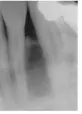

D【104-2-25】從這張根尖放射線影像看來,最不可能診斷為下列何種疾病?

(A) Ameloblastoma(B) Lateral periodontal cyst

(C) Odontogenic keratocyst(D) Globulomaxillary cyst

(超級送分題~~圖片是下頷,選項D是上頷)